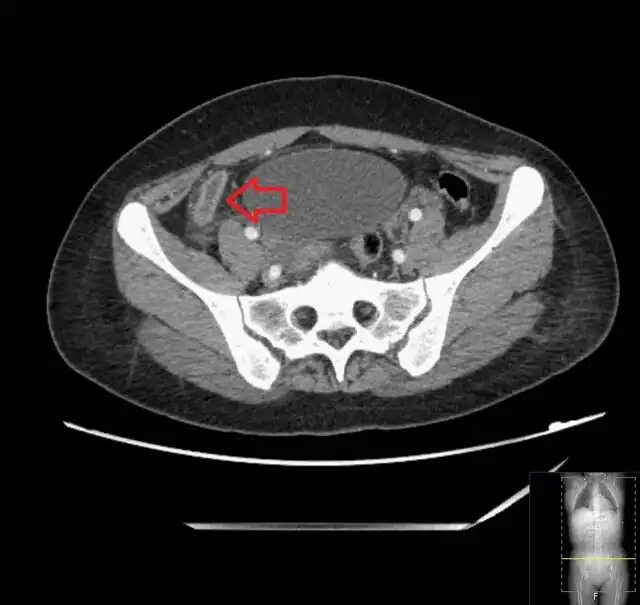

_(Radiopaedia_154713-127660_Axial_1).jpg)

Computed tomography

Where it is readily available, computed tomography (CT) has become frequently used, especially in people whose diagnosis is not obvious on history and physical examination. Concerns about radiation tend to limit use of CT in pregnant women and children, especially with the increasingly widespread usage of MRI.[49][50]

The accurate diagnosis of appendicitis is multi-tiered, with the size of the appendix having the strongest positive predictive value, while indirect features can either increase or decrease sensitivity and specificity. A size of over 6 mm is both 95% sensitive and specific for appendicitis.[51]

However, because the appendix can be filled with fecal material, causing intraluminal distention, this criterion has shown limited utility in more recent meta-analyses.[52] This is as opposed to ultrasound, in which the wall of the appendix can be more easily distinguished from intraluminal feces. In such scenarios, ancillary features such as increased wall enhancement as compared to adjacent bowel and inflammation of the surrounding fat, or fat stranding, can be supportive of the diagnosis. However, their absence does not preclude it. In severe cases with perforation, an adjacent phlegmon or abscess can be seen. Dense fluid layering in the pelvis can also result, related to either pus or enteric spillage. When patients are thin or younger, the relative absence of fat can make the appendix and surrounding fat stranding difficult to see.[52]